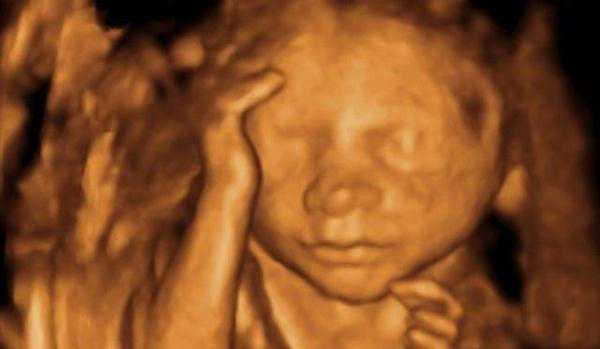

今天主要给大家讲到的,就是有关于四维彩超检查。进行四维彩超检查时,经常会发现有些小宝宝用手捂着自己的脸。

尤其是进行四维排畸检查时,很多妈妈担心小宝宝捂着自己的脸,是否会影响到检查结果。

怀孕期间,做四维彩超时,为什么胎儿经常会捂着脸?